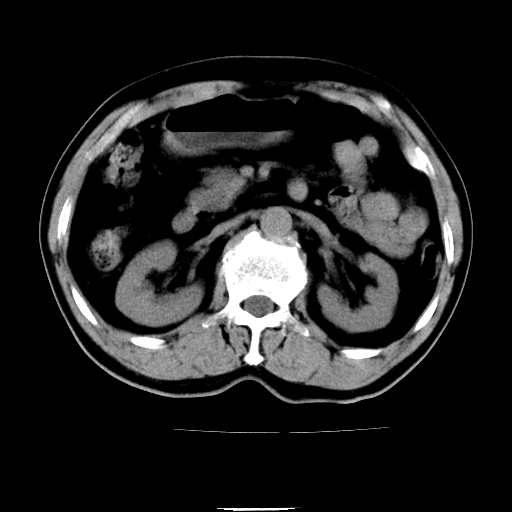

以下是引用chenqiong在2010-3-25 20:56:00的发言:[br]1、胆囊炎,胆囊息肉[br]2、肝内胆管及胆总管扩张,胆总管下端结石[br]3、十二指肠乳头旁憩室

以下是引用zxl51642在2010-3-26 10:47:00的发言:[br]胆囊炎,胆囊息肉,胆总管扩张,但未看到明显肿块,肝内胆管扩张不像恶性,炎性狭窄或阴性结石可能吧,建议mrcp,右肾小囊肿